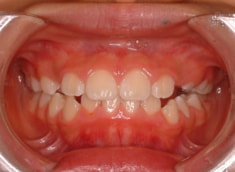

治療後(1年3ヶ月後)